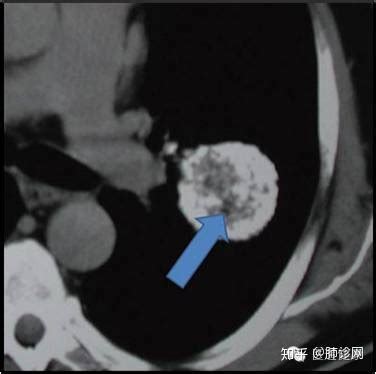

肺结节吃小金胶囊有作用吗

你好,这个肺部的结节服用小金丸是作用不大。需要看具体是病因 。需要确诊是不是结核病或者钙化灶。需要确诊病因以后制定治疗方法。